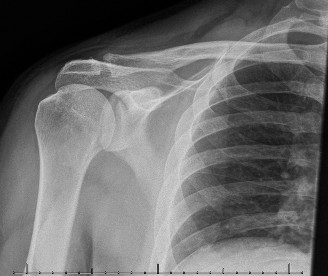

A 70-year-old, right-hand-dominant woman returns to clinic complaining of persistent, right shoulder pain. Sh…